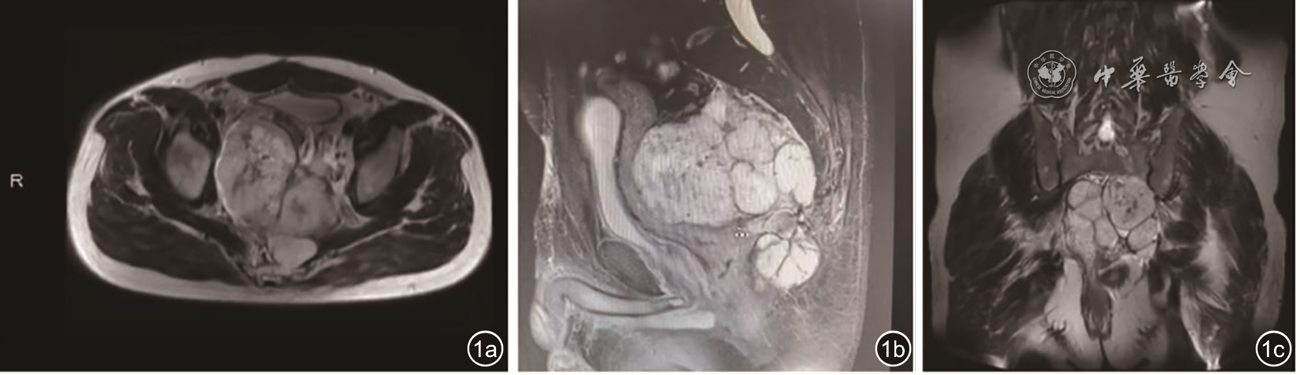

图1 影像学资料。图a为横断位显示肿瘤广泛浸润盆腔;图b为矢状位未见肿瘤椎管内累及;图c为冠状位显示腹膜后及骶前区巨大肿瘤